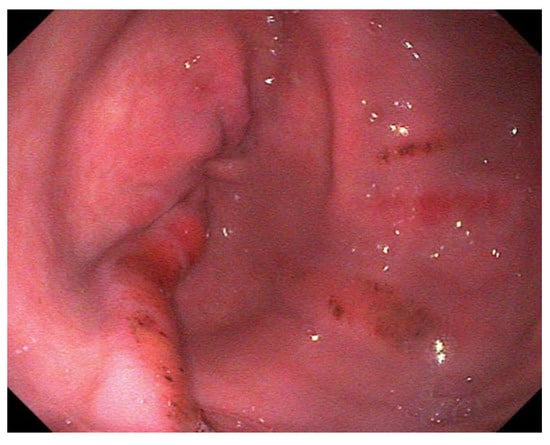

Figure 2. Multifocal, hyperemic lesions of the lesser curvature; grade 2/4 ESGD lesions. - Grade 3 Large single or extensive superficial lesions

For EGGD, the recommendation at this time remains not to assign a grade to these lesions, but instead, that lesions be described by anatomical location, distribution, severity and appearance [1]. Appearance is described as hyperemic/hemorrhagic (Figure 2 and Figure 3), erosive/ulcerated or fibrinosuppurative, and by contour; depressed, flat or raised [1]. The existence of glandular gastric polyps is also considered as a form of EGGD [120,121].

Figure 3.

Multiple, linear, flat, hemorrhagic lesions of the pyloric mucosa.